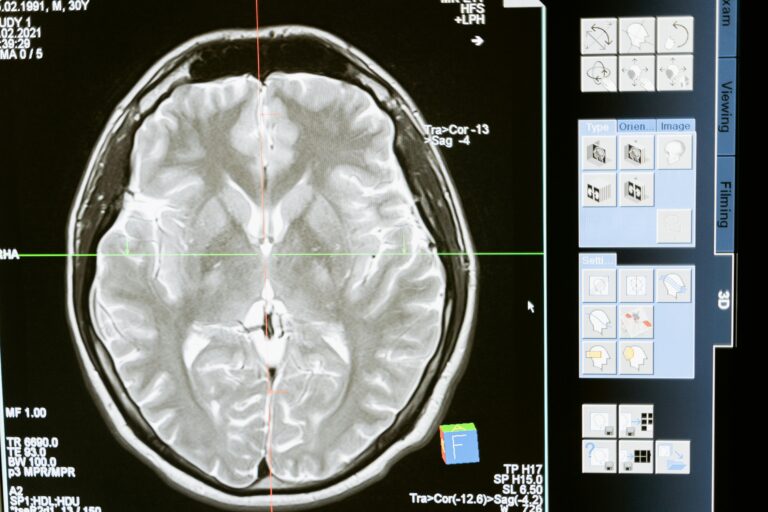

Nursing Care for the Mental Health Population

Chronic Fatigue Syndrome

Chronic Venous Insufficiency